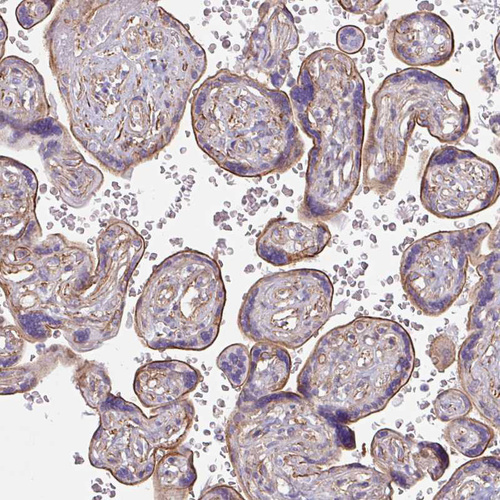

Immunohistochemistry analysis in human placenta and skeletal muscle tissues using HPA047541 antibody. Corresponding MYH10 RNA-seq data are presented for the same tissues.